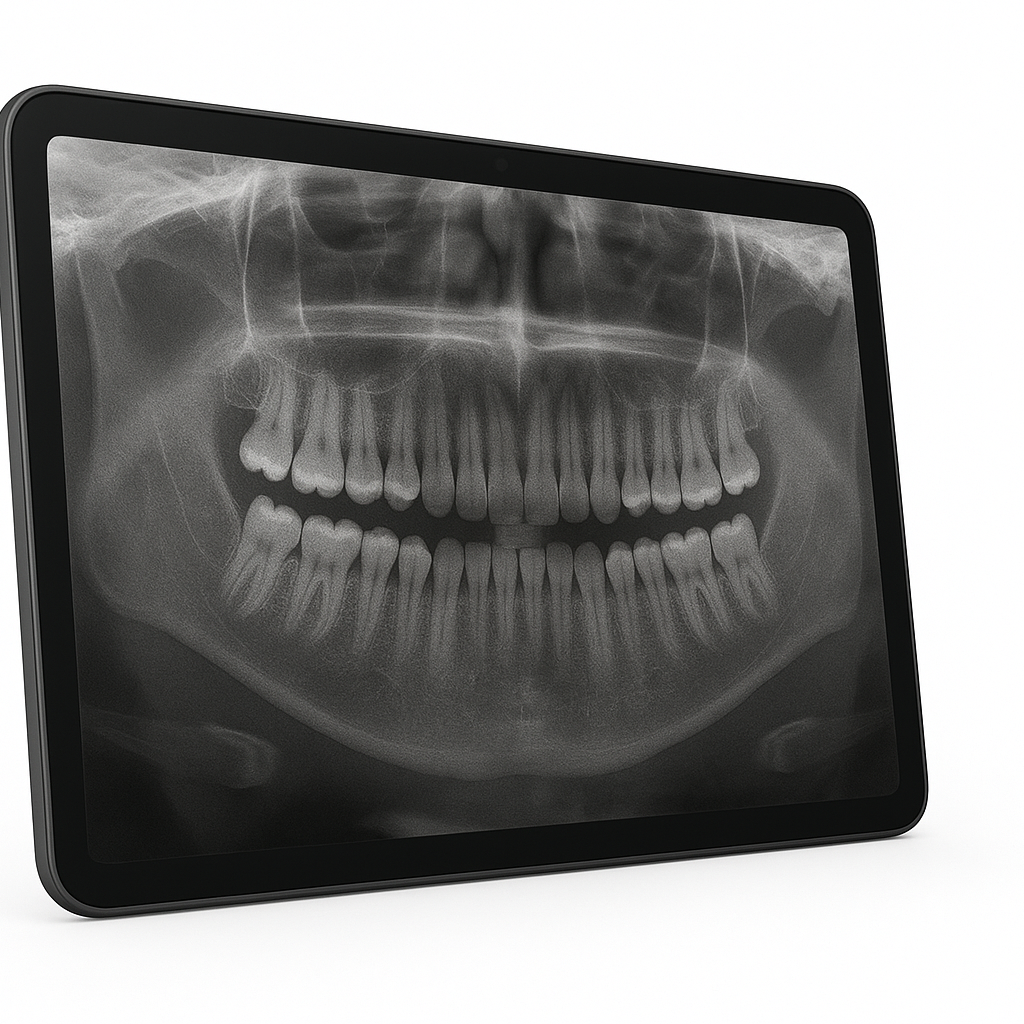

Radiografia panorâmica

Exame que mostra toda a arcada dentária, permitindo uma visão completa dos dentes, ossos e articulações. É essencial para planejamentos ortodônticos, cirurgias e avaliações gerais da saúde bucal.